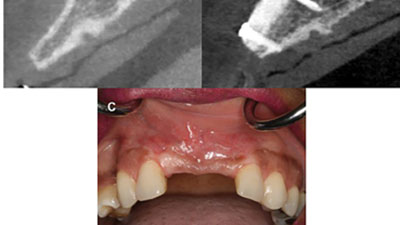

Dynamic Navigation: Predictable Implant Placement In Close Proximity To Sinus Floor

Yeganegi-OH-Fig-8 alternate text for this image

The goal of the implant surgeon is to place an implant in the ideal position, that will support a prosthesis with the best long-term prognosis, while managing important anatomical landmarks. With the aid of Cone Beam CT scans the implant surgeon is able to evaluate, in three dimensions, the ridge, important anatomy, as well as … Read more